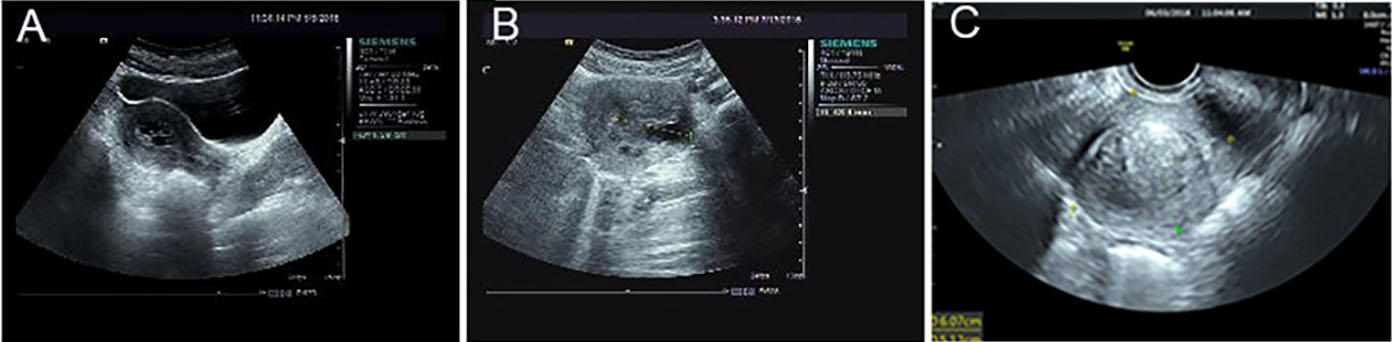

Fig. 1.Ultrasound tomographs of the patient. (A) At the age of 21, the patient’s first ultrasound examination showed a mass

with mixed echogenicity in the uterine cavity of 2.0

menstrual cycle or menstrual period. Ultrasound demonstrated two hypoechoic

nodules in the posterior wall of the uterus, 4.3